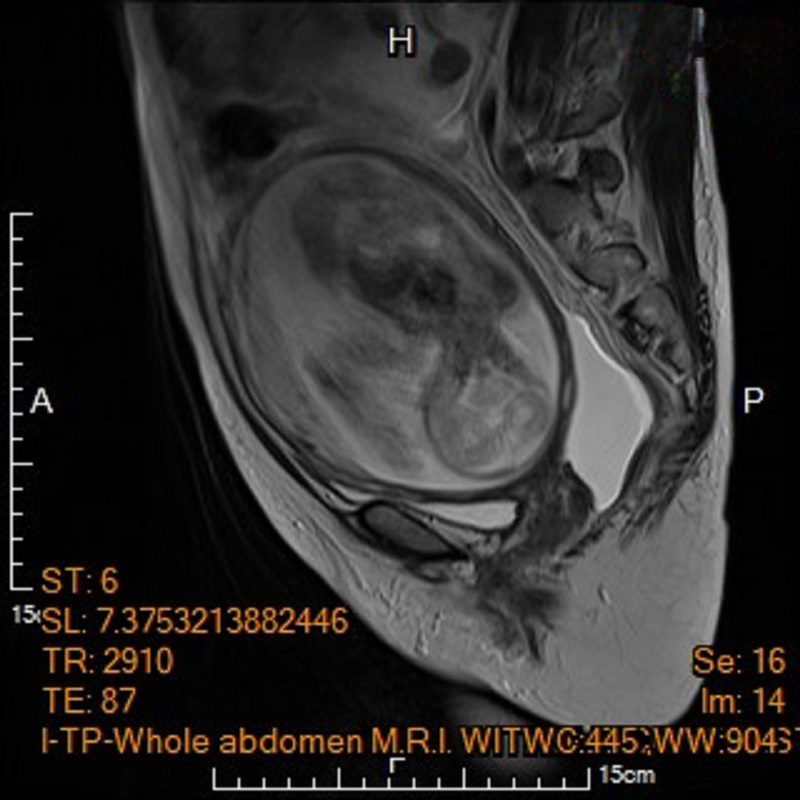

為該名孕婦產檢的馬偕紀念醫院高危險妊娠科資深主治醫師王亮凱表示,李小姐在妊娠20週進行第四次例行性產檢時,腹中胎兒發育情況一切正常,但超音波檢查意外發現孕婦腹腔內積滿大量腹水,及左側下腹部有一個15公分大小、邊界模糊、結構複雜的卵巢腫瘤,孕婦反映有明顯的進食與呼吸困難疑似腸胃道問題,為求謹慎,針對腹水檢體進行細胞檢驗,雖未能於腹水內發現癌細胞,腹部核磁共振影像顯示腫瘤疑似來自左側卵巢,且惡性風險極高,高度懷疑是懷孕中合併卵巢癌。

▲左圖:孕婦電腦斷層呈現腹水與卵巢腫瘤,右圖:電腦斷層顯示子宮內胎兒